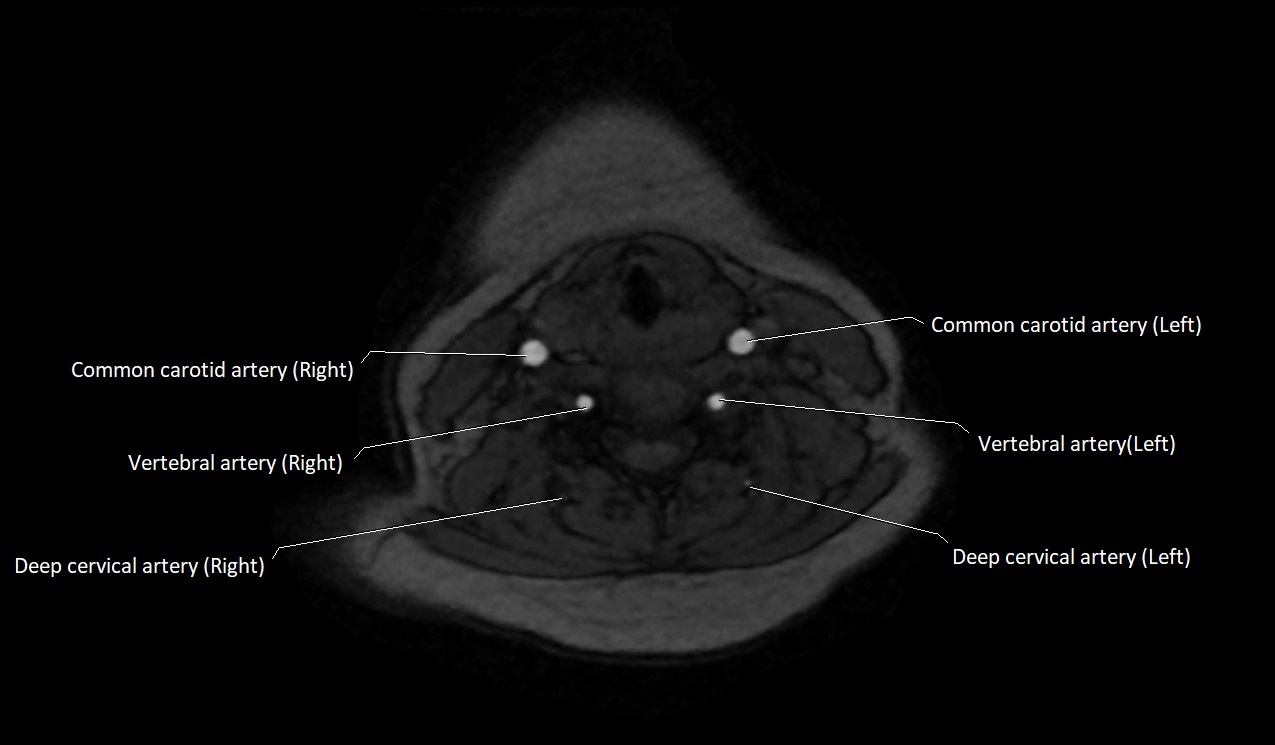

MRI Appearance:

• T1-Weighted Images:

• Appears as a tubular, hypointense (dark) structure relative to muscle

• May show flow void if the blood flow is fast

• T2-Weighted Images:

• Typically hypointense or isointense to muscle, but can be hyperintense if slow flow or stasis is present

MRI images

image